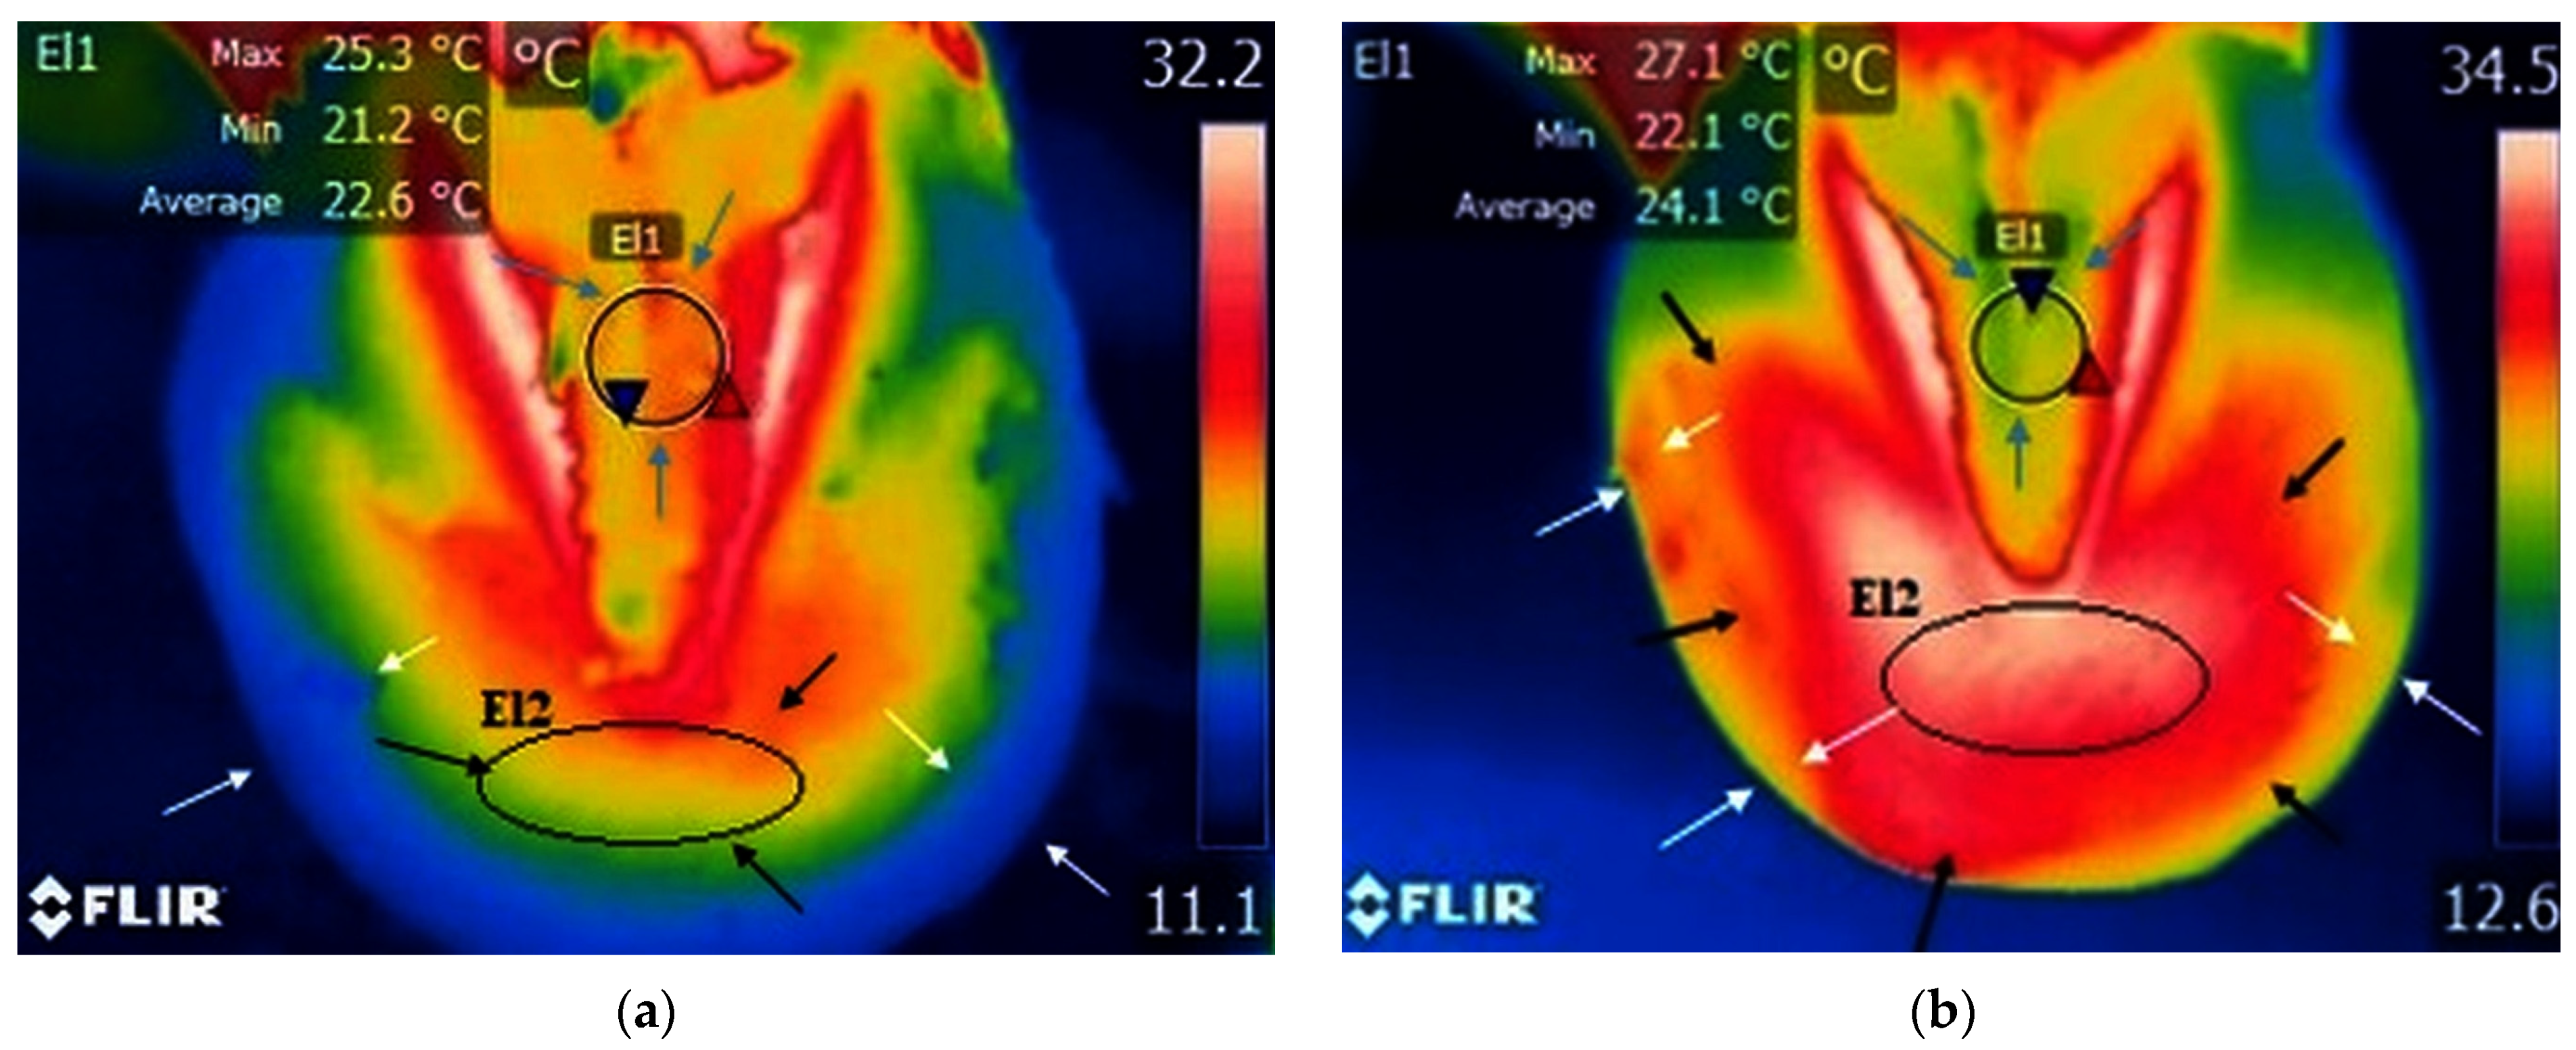

A small area of increased temperature was noticed between the frog and the hoof wall, which corresponds to the toe area, in the study group with palmar foot pain (Figure 3a and Table 1). The m.m.v.t. of the toe area was 20.6 °C.

Figure 3.

Study group, limbs with palmar foot pain: (a) sole surface before training—small surface of increased temperature in the frog area (blue arrows) and toe area (black arrows); reduced temperature along the hoof wall (white arrows); minimum temperature recorded in the area—blue triangle spot; maximum temperature recorded in the area—red triangle spot; (b) sole surface after training—increased temperature and wider surface of increased temperature in the toe area (black arrows); no obvious changes in local temperature in the frog area (blue arrows); increased temperature along the hoof wall (white arrows); minimum temperature recorded in the area—blue triangle spot; maximum temperature recorded in the area—red triangle spot.

In horses with palmar foot pain, the surrounding temperature was not raised in the frog area (Figure 3a and Table 1), and the m.m.v.t. in the frog area was 21.1 °C.

A larger area of increased temperature was found in the toe region in horses with palmar foot pain (Figure 3b, Table 1 and Table S1). The m.m.v.t. for the toe area was 27.7 °C.

In the study group with palmar foot pain, a smaller area of lowered temperature was found in the frog area (Figure 3b, Table 1 and Table S4), with m.m.v.t of the frog at 22.2 °C.

In horses with palmar foot pain, before training along the hoof wall, there was a drop in temperature, and after the training, an increased area of high temperature can be seen along the hoof wall (Figure 3).